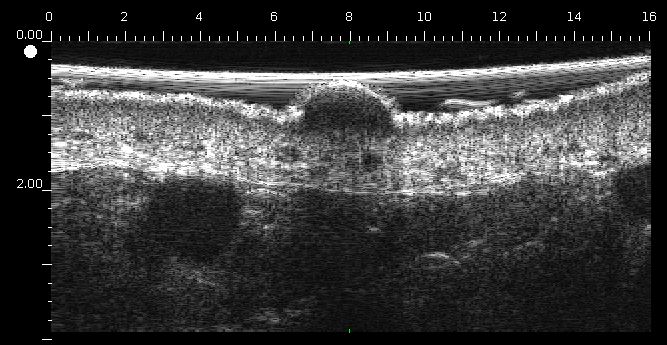

Tumeur

Echographie hypoéchogène, avec échos peu denses. L’écho d’entrée est peu marqué voire absent (absence de kératose, ulcération).

Mélanome ulcéré sur l’avant bras (épaisseur mesurée à 3.68 mm à l’échographie, épaisseur histologique).

Lésion infiltrant le derme.